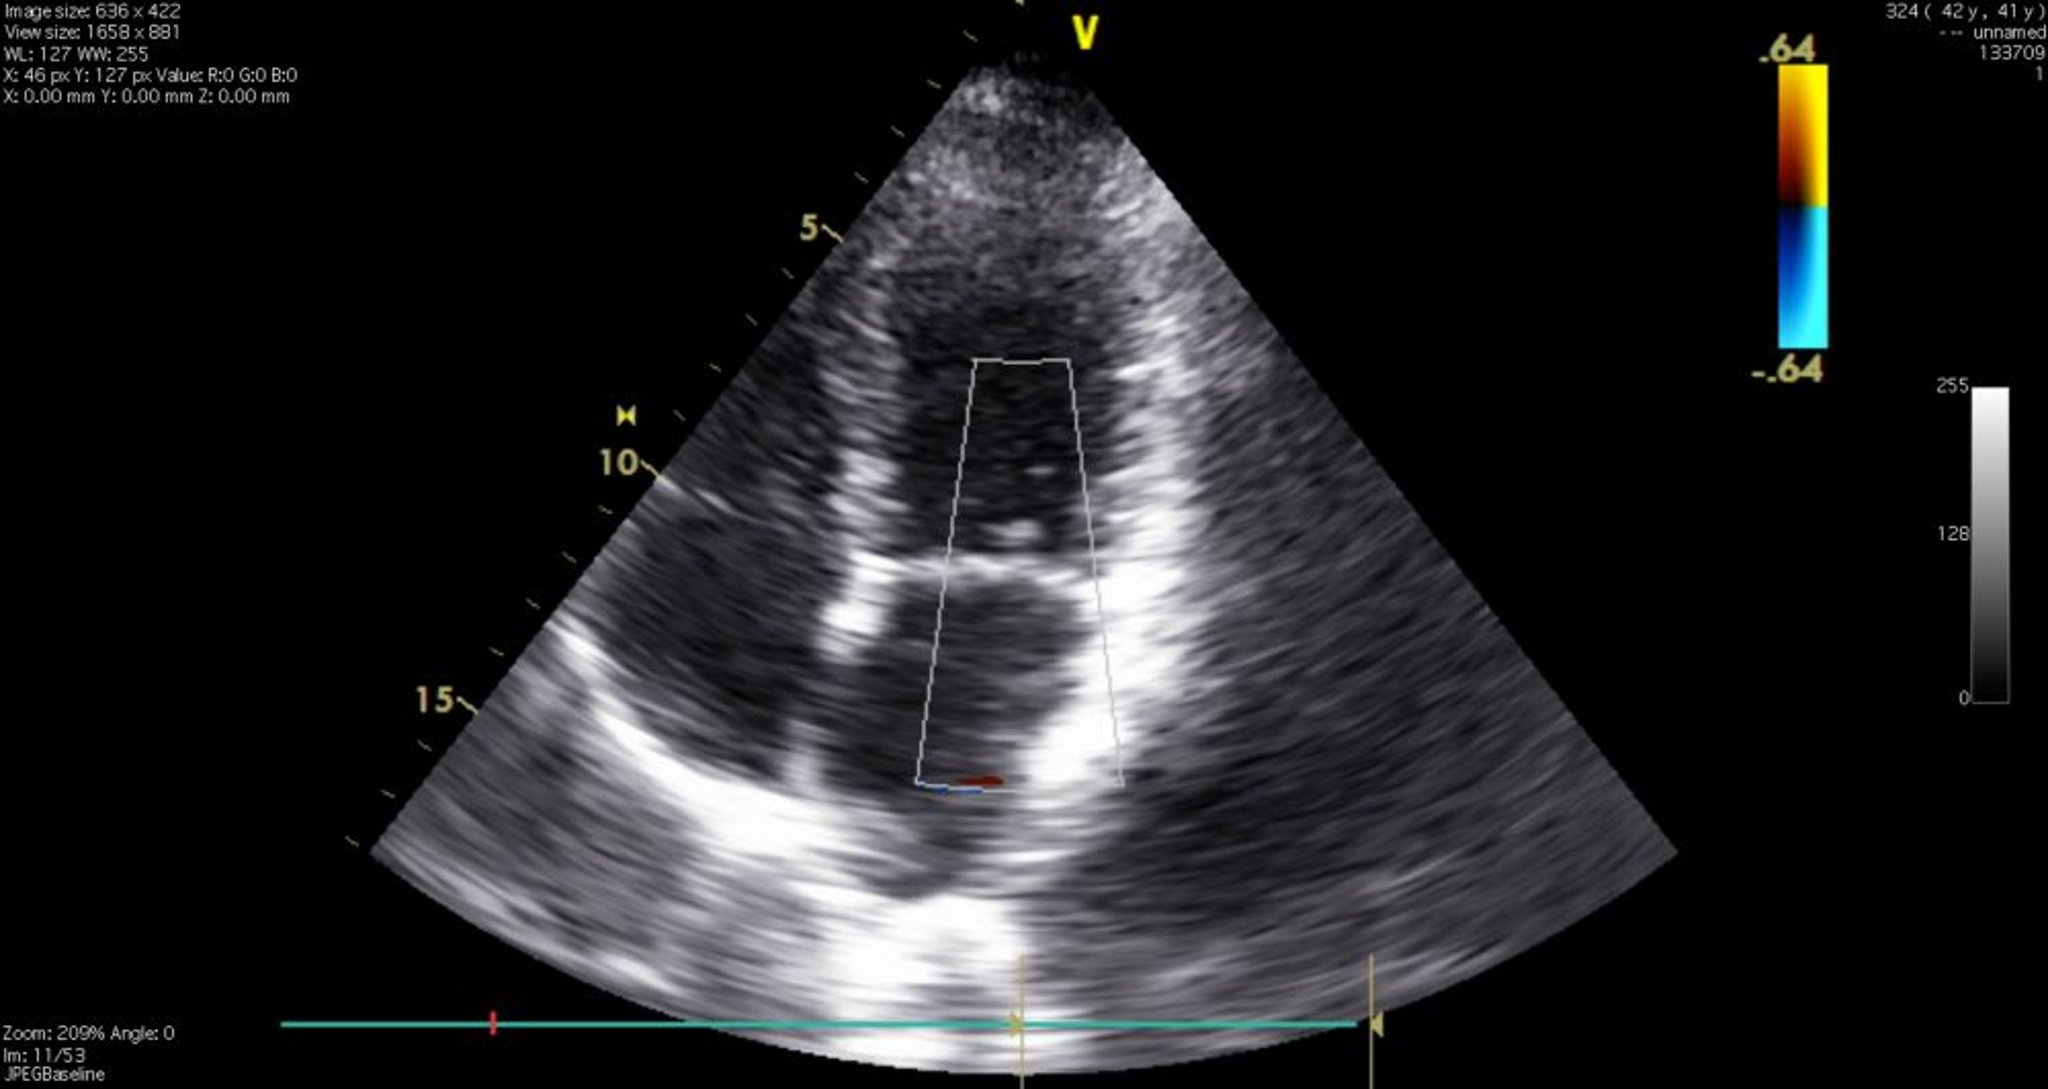

Эхокардиограмма (4-камерная проекция)

На этом изображении показаны все 4 камеры сердца, а также трикуспидальный и митральный клапаны. 1 = правый желудочек; 2 = левый желудочек; 3 = левое предсердие; 4 = правое предсердие.